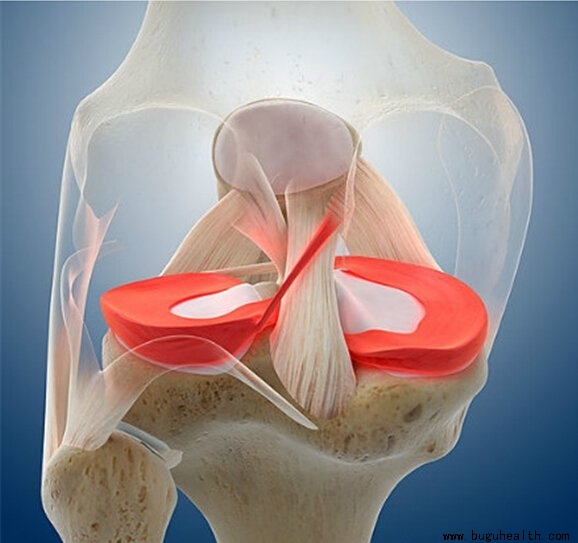

- 膝关节活动受限是比较常见的术后问题,由于术后长时间的制动,没有及时进行正规的康复治疗而出现;膝关节活动受限会随着时间的增长而越发严重,最终会形成不可逆性挛缩需要进行手术松解。影响膝关节活动的因素有很多,比如:屈膝力量不足,肌肉延展性不好,肌肉短缩挛缩,关节粘连,关节囊紧张,髌骨活动性不足等等;有一些.....

- 落地错误评分系统(Landing Error Scoring System,LESS)是通过评估被评估者落地-起跳时的生物力学特征来鉴别其发生非接触性膝关节损伤(大部分ACL损伤均为非接触损伤)风险大小的临床筛查工具,其评估结果具有较高的可信度。.....